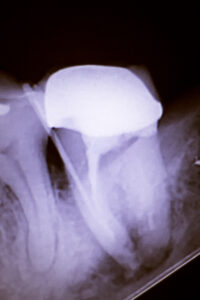

From the dentist’s side, crack-related problems can be some of the most challenging cases in everyday practice. Cracked tooth syndrome is known for variable, sometimes vague symptoms and for being difficult to confirm on X-rays.

- Dental X-rays that look normal, or nearly normal.

It is not unusual for someone to see more than one dentist, try different adjustments or restorations, and still have symptoms before a cracked tooth is finally identified. In some cases, a 3-D scan (CBCT), transillumination, or special dyes are needed to make the crack visible. Other times, the true extent of the problem is only discovered after an old filling or crown is removed, or when a narrow, deep periodontal pocket appears along the root.

Not all cracks are equal. Tiny craze lines in the enamel are extremely common and are usually harmless. Deeper cracks that extend into the dentin, or all the way into the pulp, are more concerning:

- Shallow structural cracks may cause biting sensitivity but can often be stabilized with an onlay or crown.

- Cracks that reach the pulp can inflame or infect the nerve inside the tooth, leading to lingering pain, swelling, or an abscess if bacteria enter.

- Vertical root fractures that extend down the root often have a poor long-term prognosis and may require extraction.